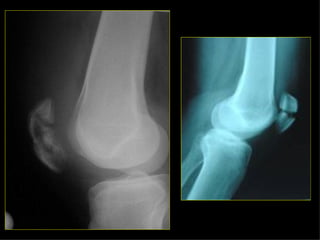

Estudio radiológico Ninguna zona de sospecha de fractura debe tener menos de dos proyecciones con 90º entre sí. En los huesos largos (pareja en extremidades), se deben incluir ambos en su totalidad. En fracturas de extremidades son a veces necesarias proyecciones del lado normal (niños).

Estudio radiológico El mecanismo de dolor referido puede equivocar en cuanto a la situación de la fractura, de importancia en lesiones de cadera y rodilla. Las proyecciones tangenciales son importantes en algunos huesos (planos). Deben incluirse las articulaciones más próximas a la fractura. En fracturas articulares, el estudio deberá incluir radiografías en AP, L, y ambas oblicuas, para detectar posibles fracturas verticales que pueden afectar a la superficie articular.

Estudio radiológico Ningunazona de sospecha de fractura debe tener menos de dos proyecciones con 90º entre sí. En los huesos largos (pareja en extremidades), se deben incluir ambos en su totalidad. En fracturas de extremidades son a veces necesarias proyecciones del lado normal (niños).

Estudio radiológico Elmecanismo de dolor referido puede equivocar en cuanto a la situación de la fractura, de importancia en lesiones de cadera y rodilla. Las proyecciones tangenciales son importantes en algunos huesos (planos). Deben incluirse las articulaciones más próximas a la fractura. En fracturas articulares, el estudio deberá incluir radiografías en AP, L, y ambas oblicuas, para detectar posibles fracturas verticales que pueden afectar a la superficie articular.